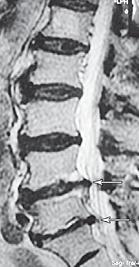

МРТ № 40

МРТ № 41

На МРТ № 40 наблюдается типичный пример развития стеноза второго типа в шейном отделе позвоночника. И аналогичная картина, только, в поясничном отделе позвоночника, отображена на МРТ № 41